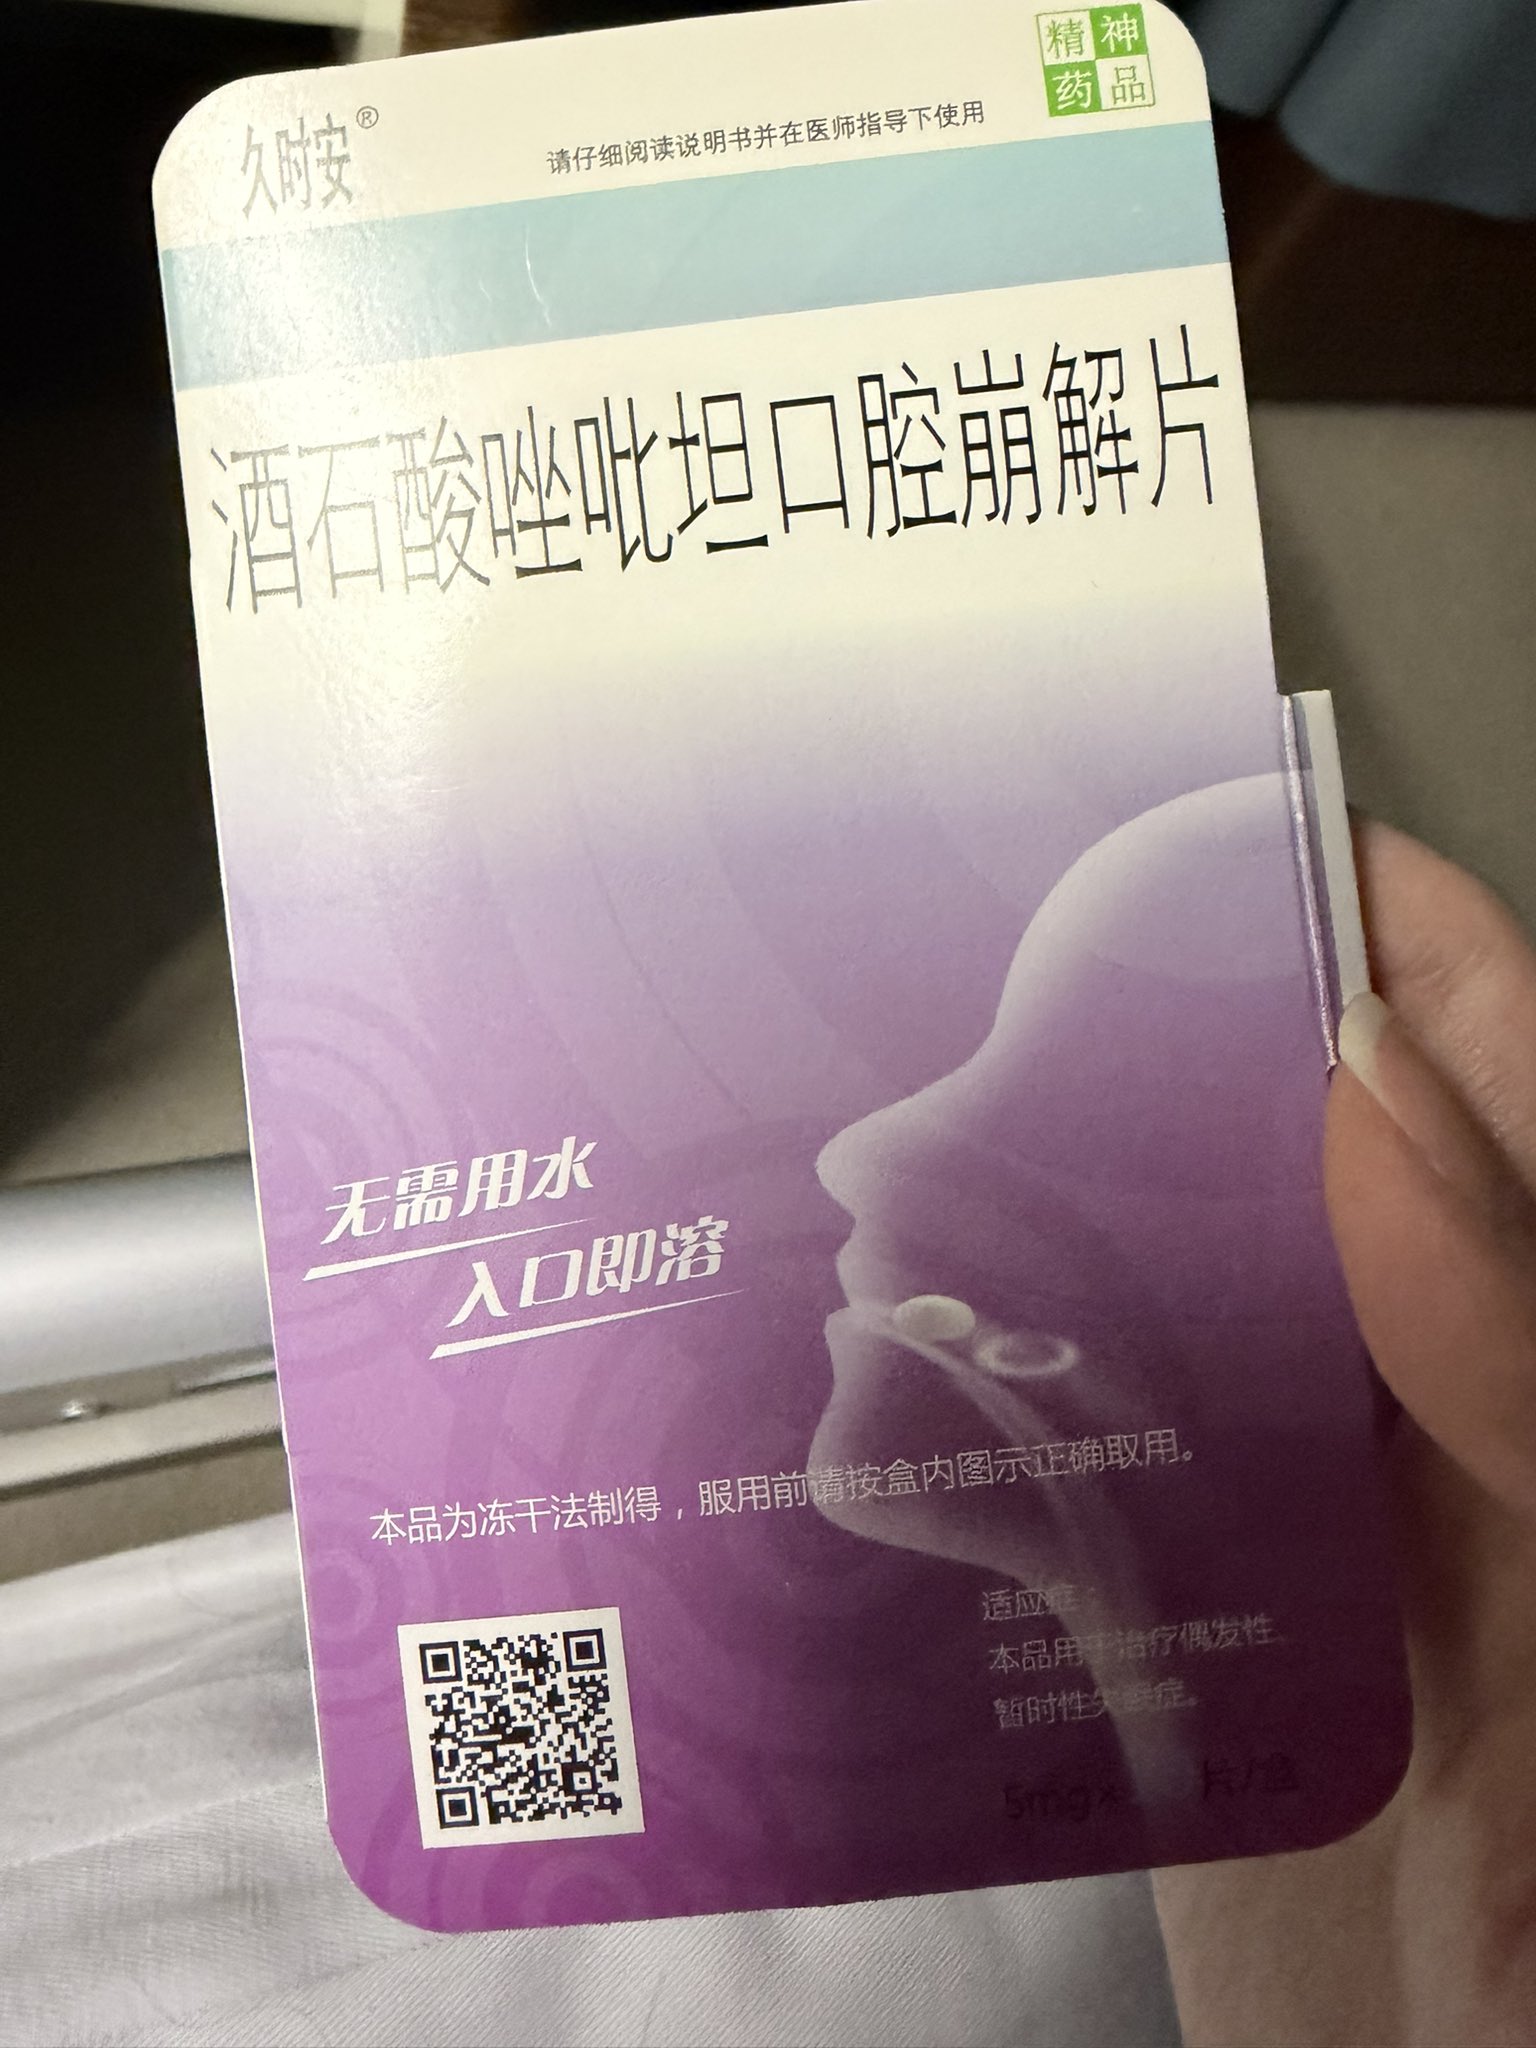

桉 @Kurokawa863905@AnIncandescence srds 酒石酸唑吡坦居然有口崩片 第一次看到诶…吃起来效果和思诺思差不多嘛

炽烈已极 @AnIncandescence@Kurokawa863905 有的。感觉起效更快一点。劣势是苦和贵